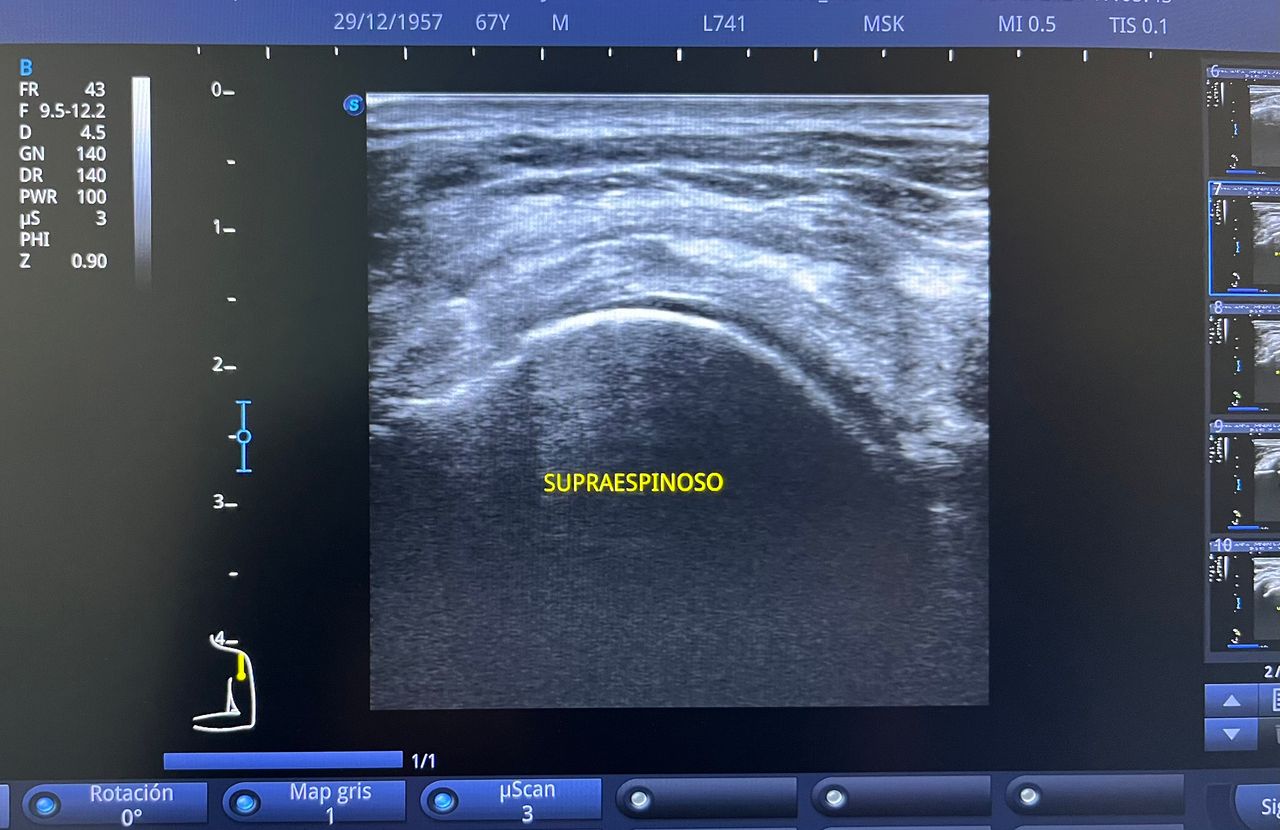

Médico general con 15 años de experiencia, master en enfermedades infecciosas y antibioticoterapia por parte de la Universidad Cardenal Herrera en Valencia, ademas de diversos diplomados en el área de Infectología y Parasitología, Urgencias, Imagenología y Medicina del Trabajo. He laborado en Hospitales y Clínicas en el área de Urgencias, en Laboratorios realizando estudios de Imagen, en especifico ultrasonidos de todo tipo desde básicos hasta avanzados incluidos los obstétricos estructurales, en Secretaría de Salud del Estado de Querétaro realizando ultrasonidos obstétricos para la detección de malformaciones en los tres trimestres del embarazo en diversos centros de salud, como médico de Empresas en el campo de Salud Laboral y actualmente en este consultorio en donde para su mejor atención y siempre buscando integrar la mayoría de las herramientas diagnosticas cuento con equipo de ultrasonido como apoyo en la exploración del paciente o como servicio diagnostico por imagen, realizo ultrasonidos convencionales (hepatobiliar (hígado, páncreas, vesícula y bazo), vías urinarias, ginecológico abdominal y transvaginal, tiroideo, prostático, testicular, pared abdominal) y especializados (dopler obstétrico en los 3 trimestres de embarazo), musculoesquelético en lesiones deportivas. También cuento con un equipo de electrocardiograma de 12 derivaciones para monitoreo completo del funcionamiento cardiaco, espirometria para evaluar la función pulmonar en la consulta, pruebas rápidas que se realizan en consultorio para detectar de forma mas precisa enfermedades infecciosas como Influenza A y B, covid19, infecciones urinarias, dengue, zika, chikungunya. Cuento con diversas vacunas para prevención de enfermedades. Siempre con el objetivo de dar el mejor servicio y atención a su salud. Lo espero en consulta para escucharlo y estudiar su caso de la forma más completa posible, estoy seguro de que tendremos las mejores opciones para su tratamiento. Mi tranquilidad es que usted se vaya con todas sus preguntas e inquietudes resueltas.